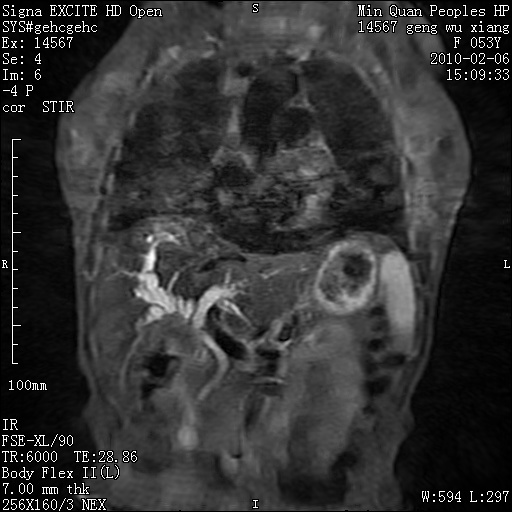

标题: MRI2762:胆道梗阻原因?

f,53y,全身黄染多日。

高位胆道梗阻 胆管癌可能性大

支持 高位胆道梗阻 胆管癌可能性大。